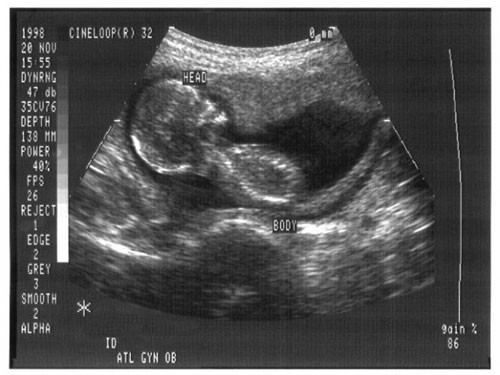

| Trẻ trong quá trình bào thai có thể nghe được âm thanh từ bên ngoài tử cung Ảnh: ARSTECHNICA - CDC |